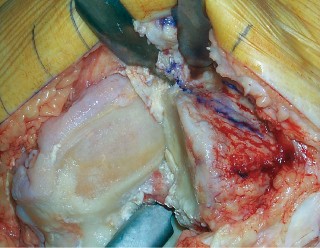

- فتح المفصل (Arthrotomy): يكون الفتح خطيًا وموازياً لألياف الوتر الرضفي، ويمتد إلى عظم الظنبوب وإلى الجزء السفلي من الرضفة.

- تحرير الأنسجة الرخوة: يتم قطع الغضروف الهلالي لتحرير الأنسجة الرخوة من عظم الظنبوب، ويتم تطوير سديلة تحت السمحاق في نمط دائري حول الظنبوب. يُمدد هذا التحرير خلفيًا لضمان توازن الأربطة.

-

تصحيح التشوه:

الهدف هو تحقيق تصحيح طفيف للتشوه، مع وجود رخاوة كاذبة طفيفة عند تطبيق ضغط تفحجي في نهاية الإجراء. يجب تجنب التصحيح المفرط.